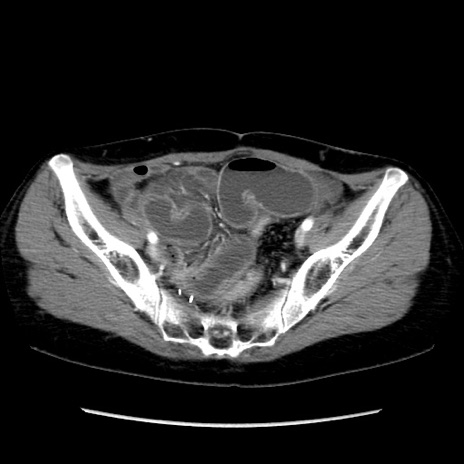

冠状断像

【症例】40歳代 女性

【主訴】上腹部痛、嘔気・嘔吐

【現病歴】約9時間前頃から急に上腹部痛、嘔気、嘔吐が出現。改善しないため救急要請。

【既往歴】子宮頚癌(広汎子宮全摘術、放射線療法)、腸閉塞

【身体所見】腹部:平坦、軟、腸雑音亢進、上腹部を中心に腹部全体に圧痛あり。

【データ】WBC 8400、CRP 0.03